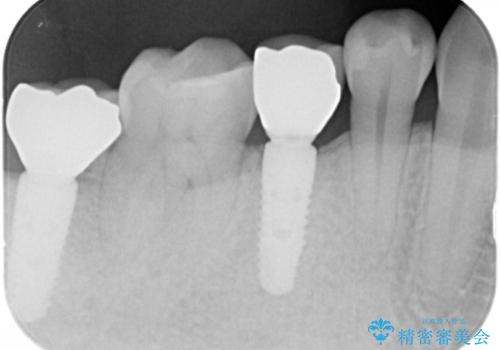

- 奥歯(右下5)のインプラントをご希望し来院された患者様です。

なるべく低予算でとのご希望により、アルファタイトインプラント(保証期間:3年)による治療を行いました。

- ¥320,000 (インプラント、既成アバットメント、仮歯、クラウン)費用は治療当時の料金となります

自然な仕上がりと咬み心地に喜んで下さいました。

「低予算でしっかりした治療を受けることができた」とご満足頂けました。

インプラントの種類:アルファタイト

クラウンの種類:オールセラミッククラウン スタンダード